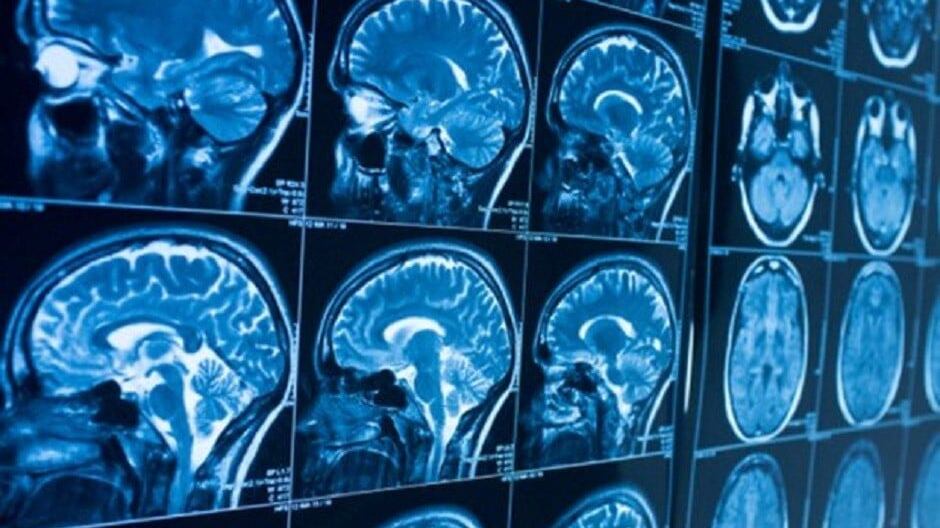

Uma nova ferramenta de Inteligência Artificial (IA), desenvolvida no âmbito do projeto internacional Multicentre Epilepsy Lesion Detection (MELD), está transformando o diagnóstico da epilepsia infantil. Este algoritmo é capaz de identificar anormalidades cerebrais sutis que, até agora, muitas vezes não eram detectadas em ressonâncias magnéticas convencionais, mesmo após serem revisadas por radiologistas especializados.

A ferramenta, chamada MELD Graph, foi treinada em 1.185 ressonâncias magnéticas (quase metade delas de menores) de 23 centros de epilepsia ao redor do mundo. Seus recursos foram testados em um estudo publicado no JAMA Neurology.